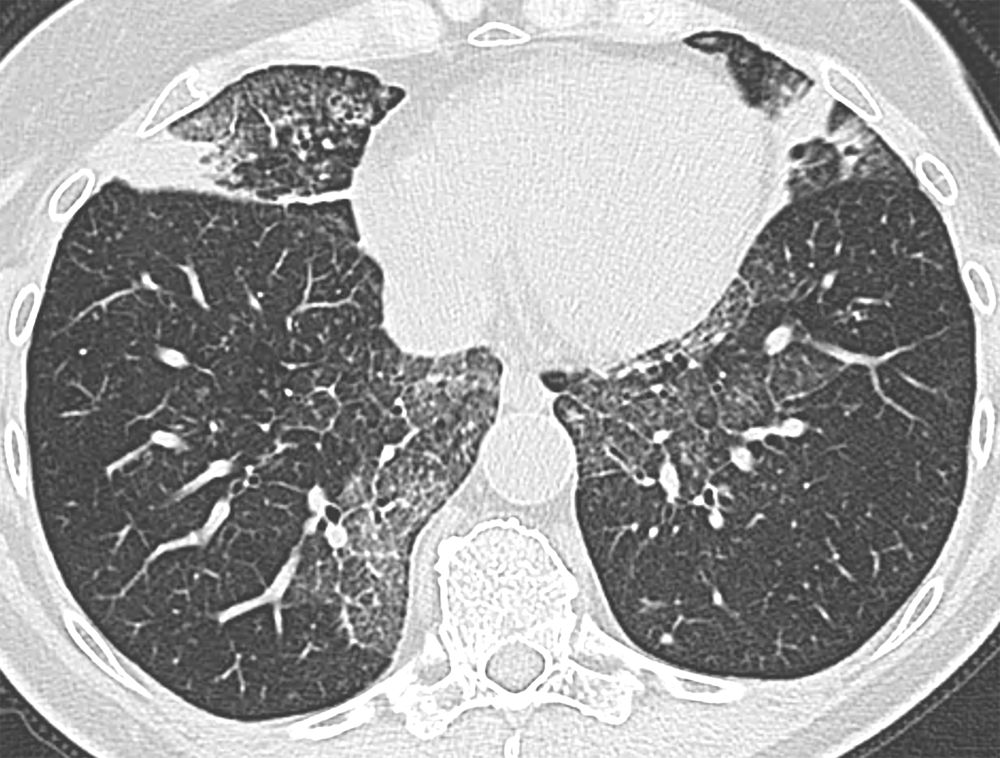

Junior #radres- normal or abnormal? Diagnosis? 🧐

#radiology

#chestrad